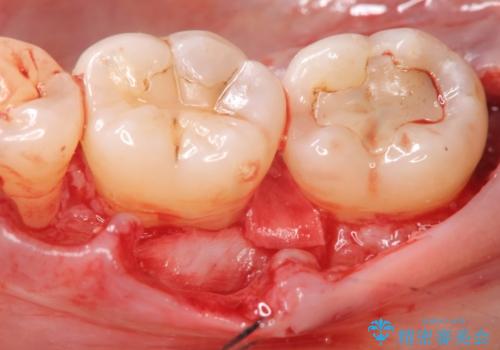

歯を抜かずに残せるよう、再生療法・歯周ポケット除去手術を計画します。

再生治療を行うことで、吸収した骨を再生し歯を保存できることがあります。